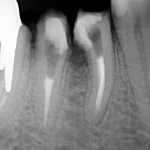

Poniżej zdjęcie rentgenowskie

po zabiegu premolaryzacji. Widzimy już dwa oddzielne zęby.

Gojenie trwa około roku.

Jeśli zdjęcie rentgenowskie

wykonane po roku pokazuje wygojoną kość a pacjent nie ma żadnych dolegliwośći,

można przystąpić do odbudowy protetycznej.

Wykonuje się dwie mniejsze

korony zamiast jednej, co umożliwia prawidłowe czyszczenie. Zęby wyglądają

naturalnie i spełnieją swe funkcje.